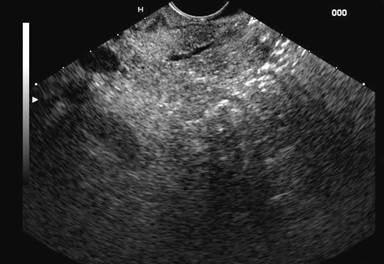

concluded that linear EUS is a

promising test for the diagnosis of pancreas divisum. In our experience also,

the diagnosis of pancreas divisum can be excluded if the pancreatic duct can be

followed from the major papilla to the pancreatic body or crosses the

endosonographic border between the ventral and dorsal pancreas (Figures 2 and 3).

Figure 3. Linear EUS:

pancreatic duct seen crossing the endosonographic border between hypoechoic

ventral anlage and brighter dorsal anlage. |